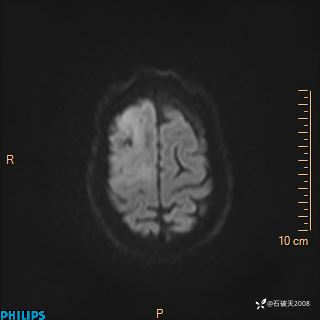

2024.2.21MR

DWI